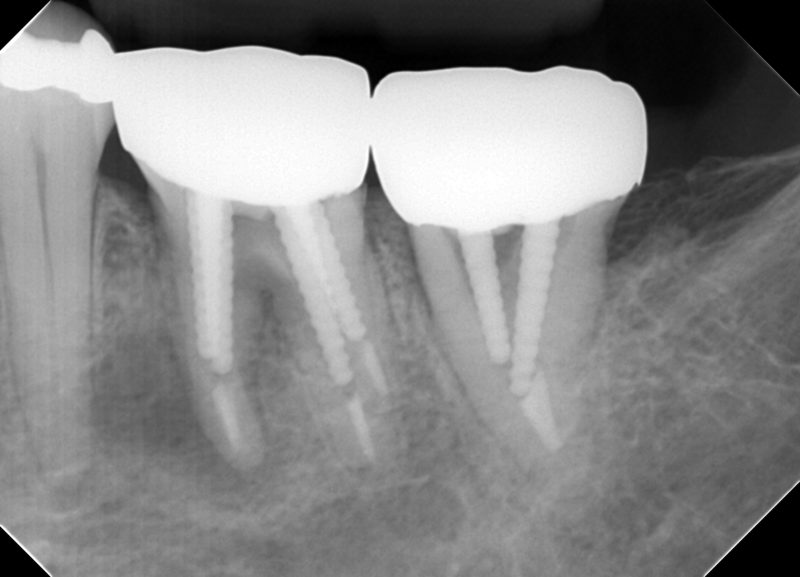

レントゲンから読み取れることは、スクリューは除去できそうだが骨の吸収具合から歯根破折を疑いました。

4本全てのスクリューを安全に取り除きました。

レントゲン写真での途中経過では骨の回復傾向が認められました。